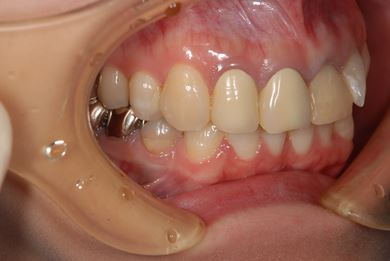

| 性別/年齢 | 女性 / 27歳 | ||||||||||||||||||||||||||||||||

| 主訴 | 審美歯科治療を希望。歯ならびもできるかぎりそろえたい。 | ||||||||||||||||||||||||||||||||

| 治療内容 | オールセラミック4本(オールセラミック用土台4本)、メタルボンドセラミック2本(メタルボンドセラミック用土台2本) | ||||||||||||||||||||||||||||||||

| 総治療費 | 867,825円 | ||||||||||||||||||||||||||||||||

| 治療期間 | 5ヶ月 |